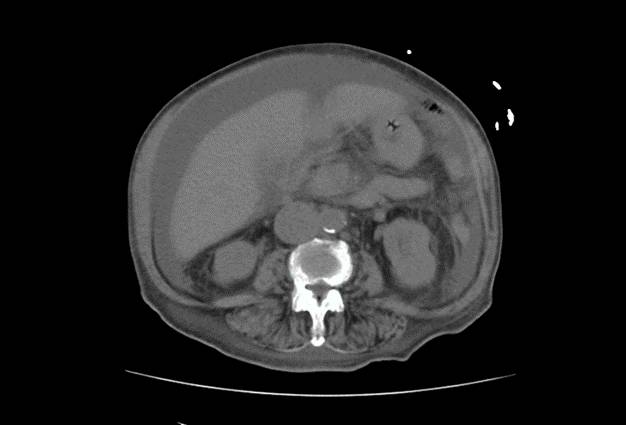

胸部+全腹平扫CT

1、双肺炎症性改变,双侧胸腔积液

2、心影增大,心包积液

3、动脉硬化

4、大量腹水,胆囊壁增厚,

5、下腔静脉增宽